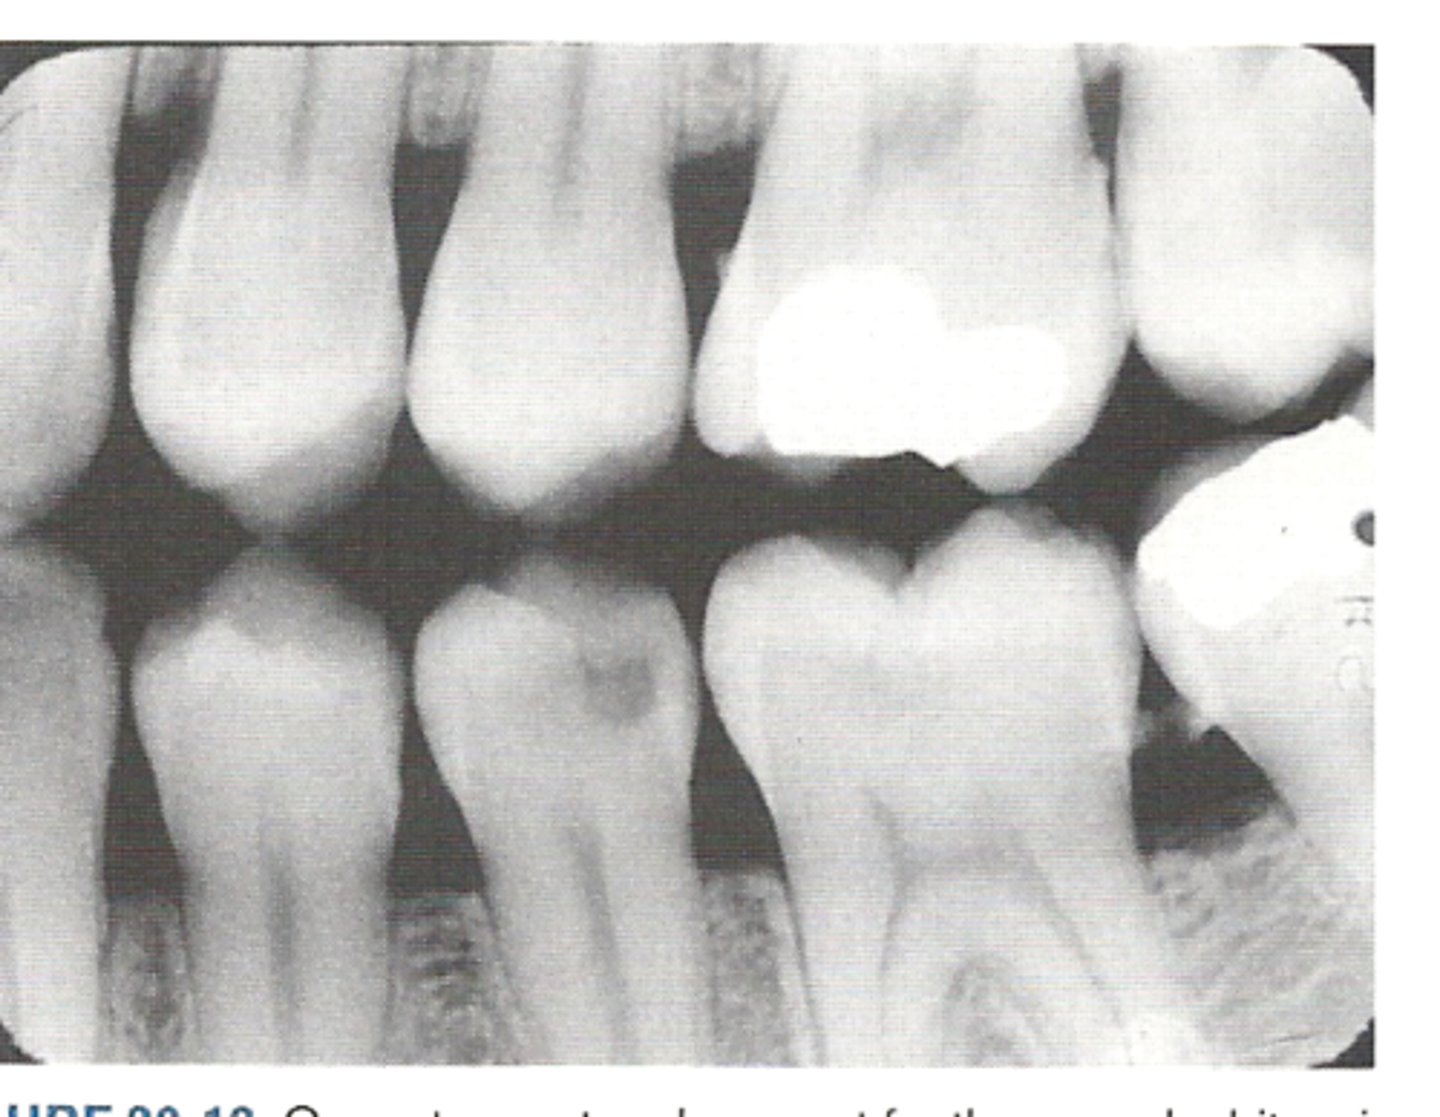

Bitewing

upper and lower crowns together and bone levels

What do we need to make sure we get with Bitewings?

crowns of both maxillary and mandibular teeth on same radiograph

Why do we take bitewings?

show caries, margins of restoratios, and alveolar crest better